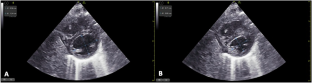

To investigate the association between lung ultrasound score (LUS) and left ventricular eccentricity index at end-systole (LVEI-s) and end-diastole (LVEI-d) in preterm infants with respiratory failure.

This prospective pilot study included 38 ultrasounds on 20 premature infants with Transient Tachypnea of the Newborn (TTN) and Respiratory Distress Syndrome (RDS) requiring non-invasive ventilation at birth. LUS, LVEI-s, and LVEI-d were obtained daily for 72 h. Linear regression analysis was performed to determine correlation.

LUS positively correlated with LVEI-s (r = 0.47, p = <0.01) and LVEI-d (r = 0.63, p = <0.01) during the 72-hour study period in the RDS group, but not the TTN group. Correlation increased over the first 24 h (LVEI-s: r = 0.69, p = <0.01; LVEI-d: r = 0.68, p = <0.01) in the RDS group.

As LUS increases, both LVEI-s and LVEI-d demonstrate measurable changes in infants with RDS. This association may enhance precision in diagnostic stratification and optimizing fluid management in neonatal lung disease.